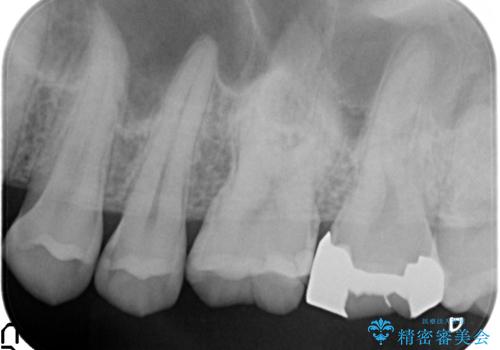

- 健診で虫歯があると言われたので診て欲しいといらっしゃった方の症例です。

左上5、6、7番目の歯に虫歯を認めたため、左上5、7はセラミックインレーによる修復を行いました。

左上6に関しては患者様の希望でパラジウムインレーによる修復を行いました。